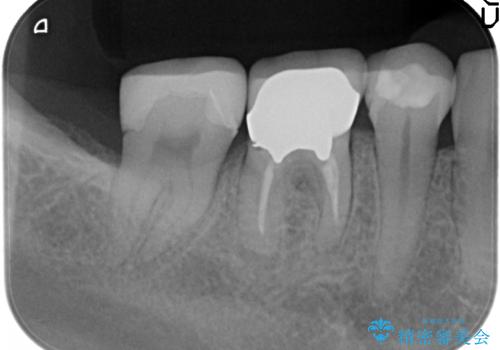

- たまに疼くことがあると他院を受診したところ抜歯を勧められたが、歯を残せないものかと当院にいらっしゃった方の症例です。

診査の結果抜歯の必要性はなさそうだったため再根管治療を行い、その後オールセラミッククラウンによる補綴を行いました。